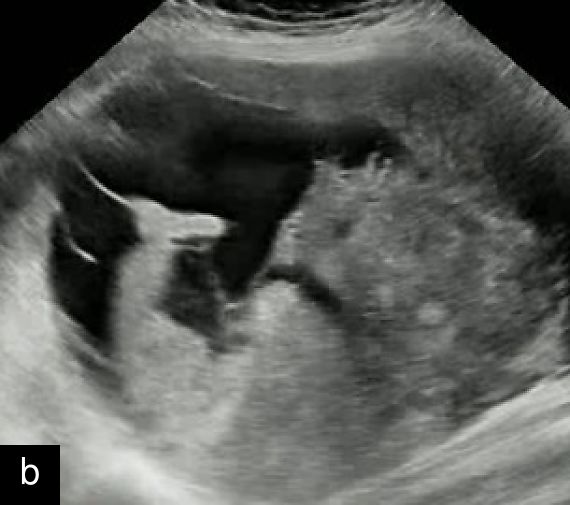

In 2019, an international group of experts conducted one of the first retrospective analyses of a relatively large cohort of histologically confirmed uterine sarcomas (n = 195; 116 LMS, 48 ESS and 31 USS), describing their most common ultrasound features.13 Malignant lesions appeared as large isolated solid masses (mean diameter, 91 mm) with inhomogeneous echogenicity of the solid tissue (77.4%), sometimes containing cystic areas (44.6%) (77% were irregular), mostly without fan-shaped shadowing or calcification (Figures 1 and 2). Although moderate-to-rich vascularization (color score 3–4) was common (67.9%), about one-third of sarcomas showed minimal or absent vascularization (color score 1–2), likely due to tumor necrosis (Figure 3). Notably, 20% were misclassified as benign, with ESS often showing normal endometrial appearance, regular margins and sparse vascularization, while USS displayed irregular margins, hemorrhagic cystic areas and absence of shadowing.13 One sarcoma was multilocular without solid components.13 The ‘cooked appearance’ of solid tissue, indicating necrosis, was observed in 21.7% of sarcoma cases13 but also appeared in leiomyomas and STUMPs, limiting its specificity.5 This sonographic feature refers to areas of inhomogeneous, hypoechoic solid tissue with absent internal vascularization, resembling the texture of cooked meat.

1

Transvaginal ultrasound images with Doppler evaluation of cases of STUMP. The images depict heterogeneous echotexture, irregular vascularization patterns and varying degrees of cystic and solid components.